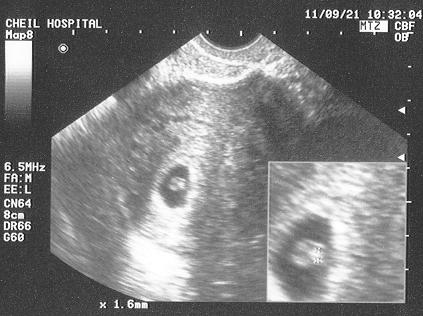

44日目に心拍確認。

心拍が確認された時の写真です。